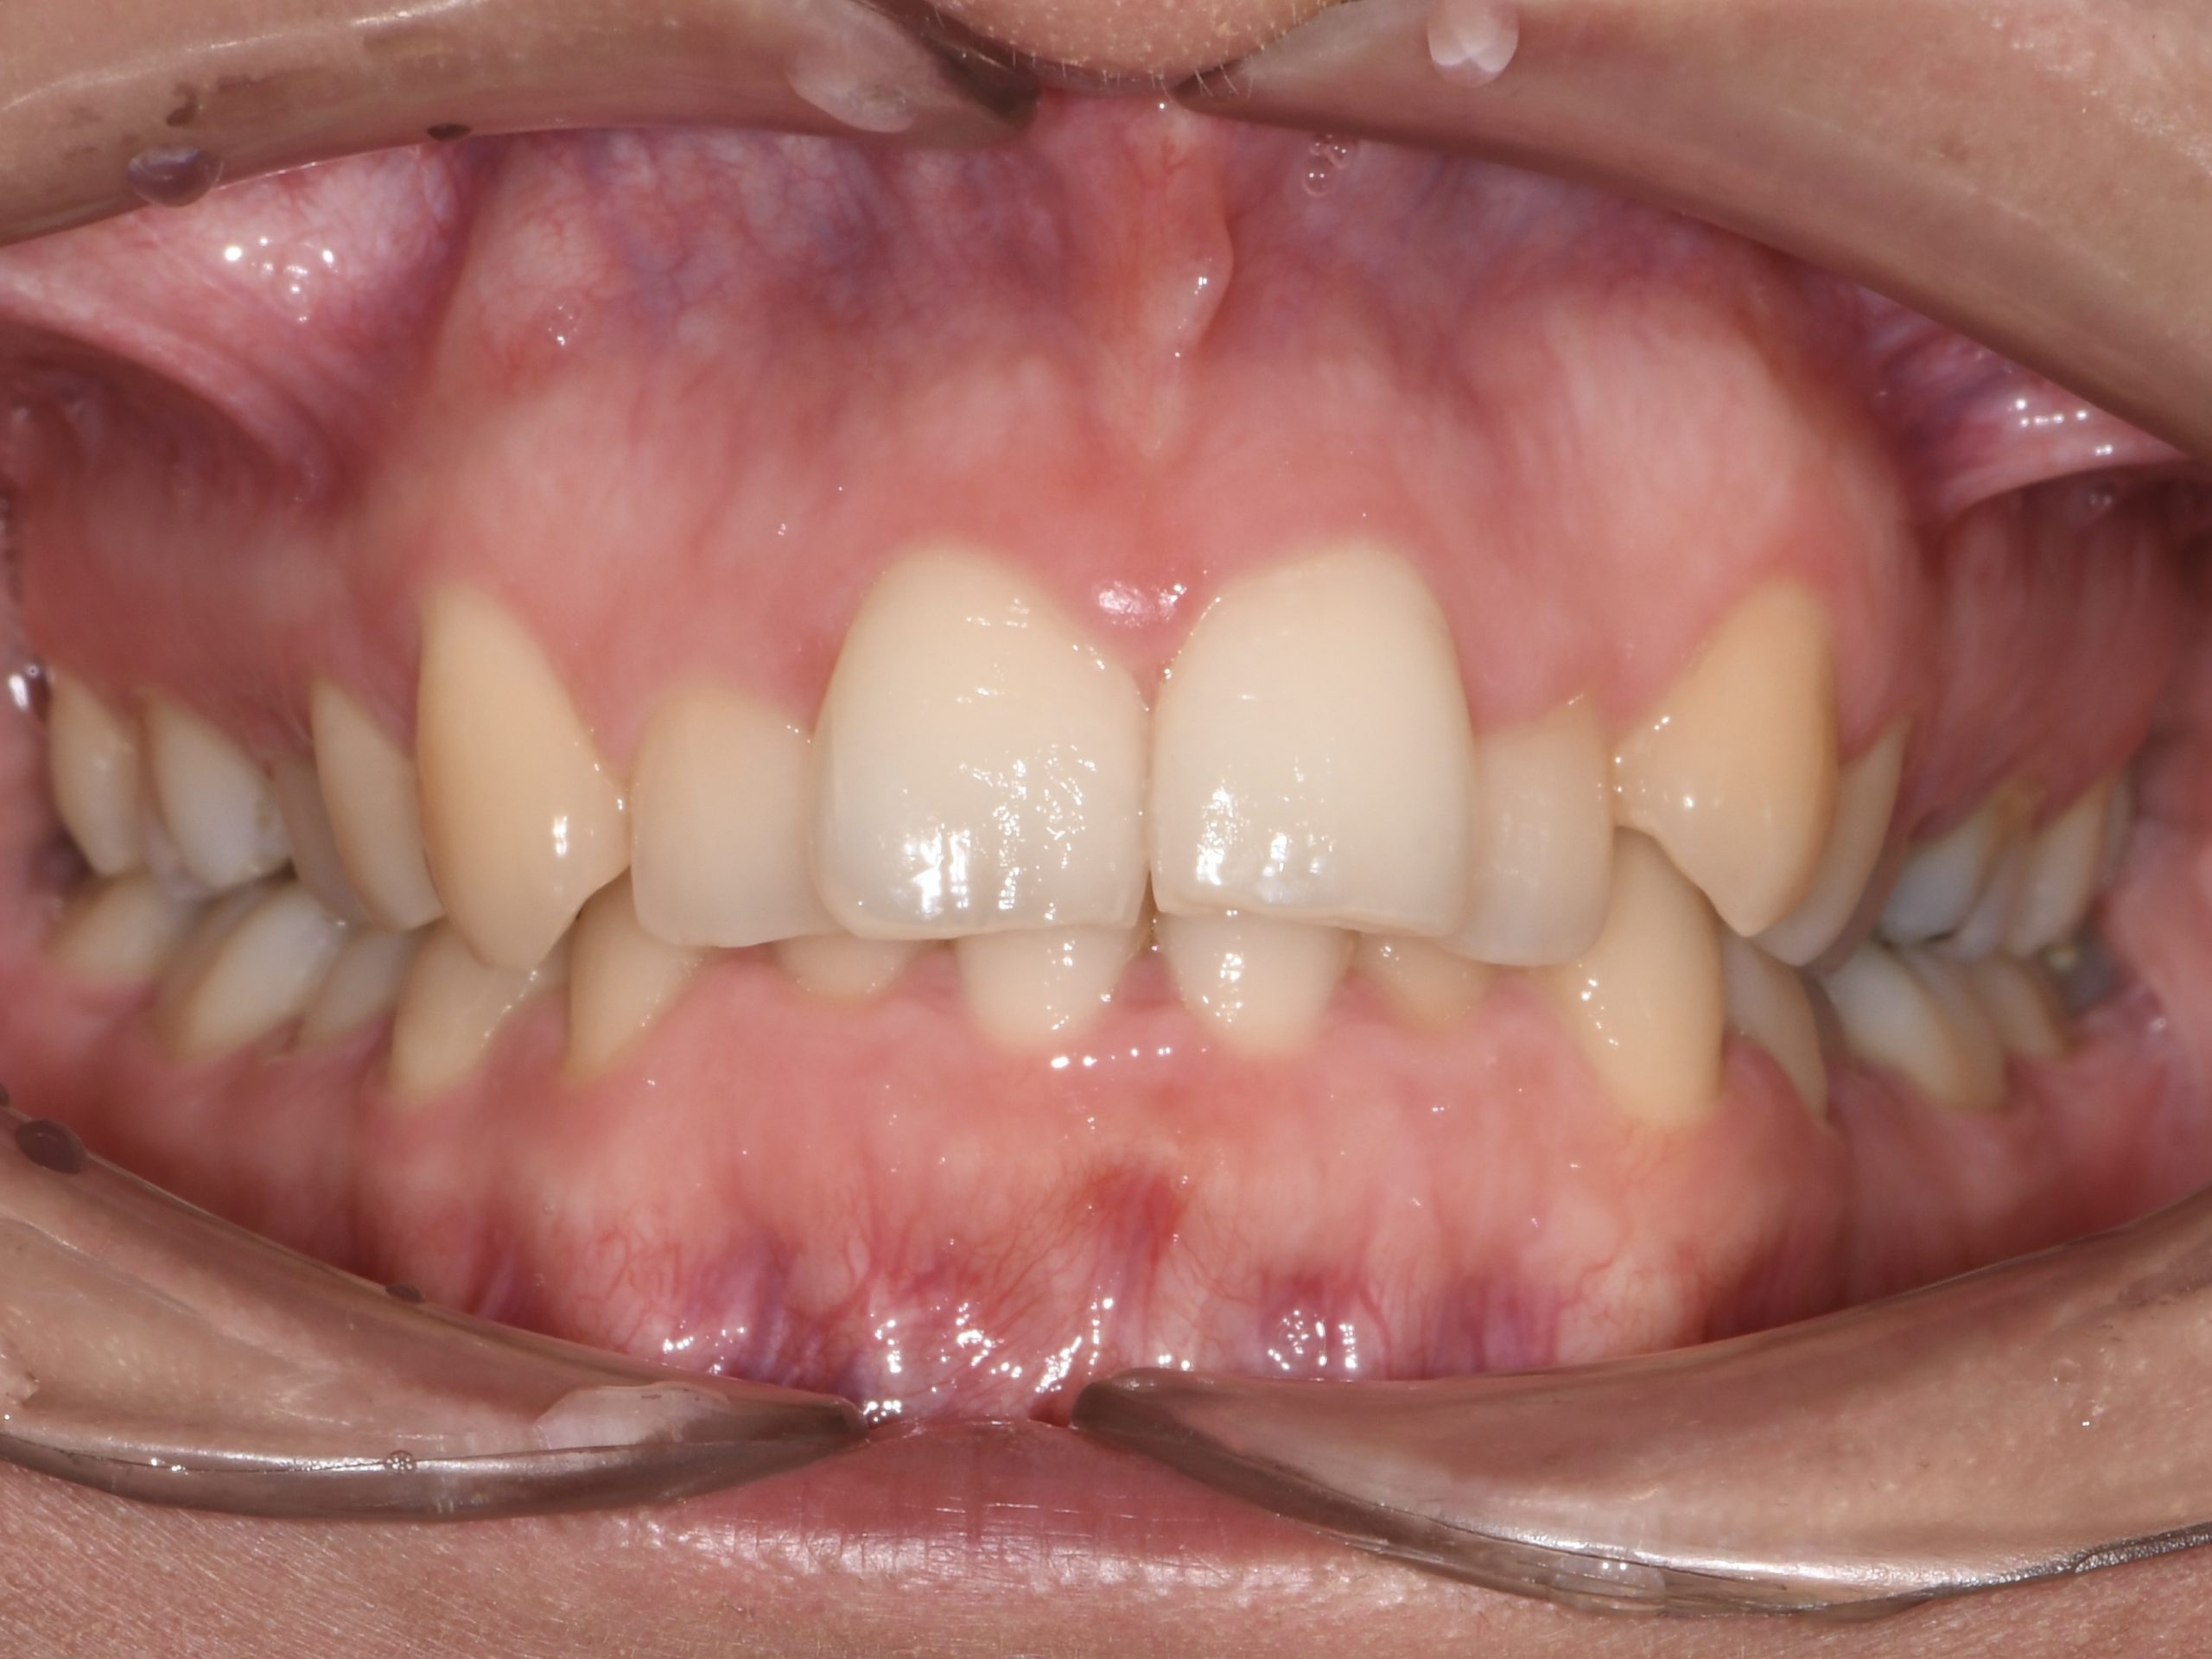

Az elmúlt évekből rengeteg szakmai referenciát tudnánk bemutatni, amelyek különböző fogszabályozási problémákat oldottak meg. Válogatva a több száz esetből, ezen az oldalon olyan képeket, információkat igyekeztünk bemutatni, amelyeknek a segítségével a jövőbeni pácienseinknek azt tudjuk üzenni: A Te fogsorod is lehet gyönyörű!

(Képeket a Pácienseink külön írásos beleegyezésével mutatjuk be!)